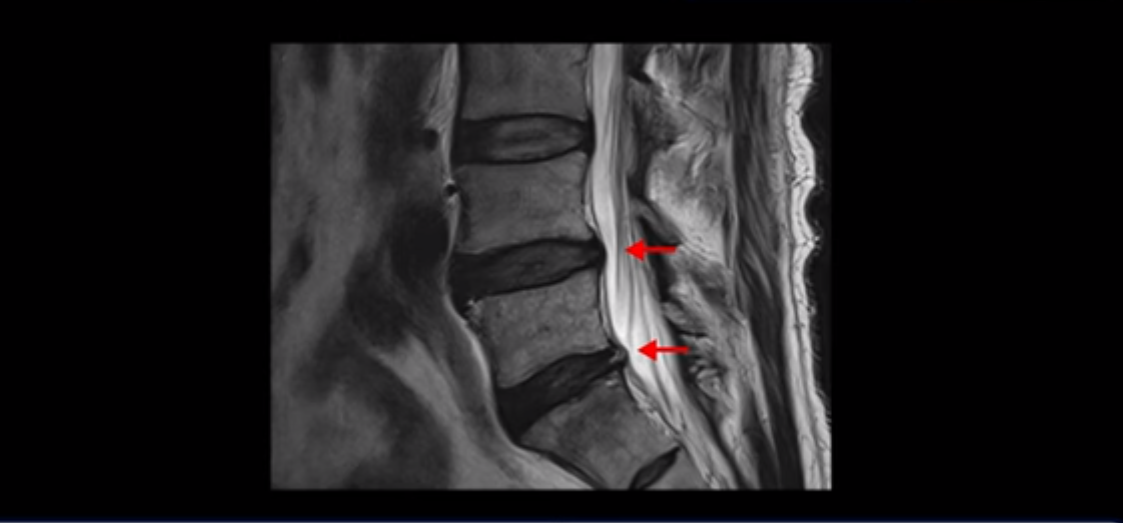

이분 허리 MRI를 보면 60세가 넘었기 때문에 퇴행이 진행은 되었지만 아주 심하지는 않습니다.

이분 왼쪽 다리가 저리고 아파서 2~3년 전부터 걷기가 힘들었는데 이분 허리 4번, 5번 마디에 신경 가지가 빠져나가는 추간공이 다른 마디에 비해서 좁아져 있습니다. 하지만 아주 심하게 좁아져 있지는 않습니다.

의사마다 MRI를 보고 얘기가 달랐다고 하는데 심하지 않다고 하는 쪽이 맞습니다. 그런데 이분은 신경 구멍 넓이에 비해 증상은 매우 심한 편입니다. 왜 그럴까요? 이 이유와 어떻게 치료하는지에 대해 지금부터 설명해 드립니다.